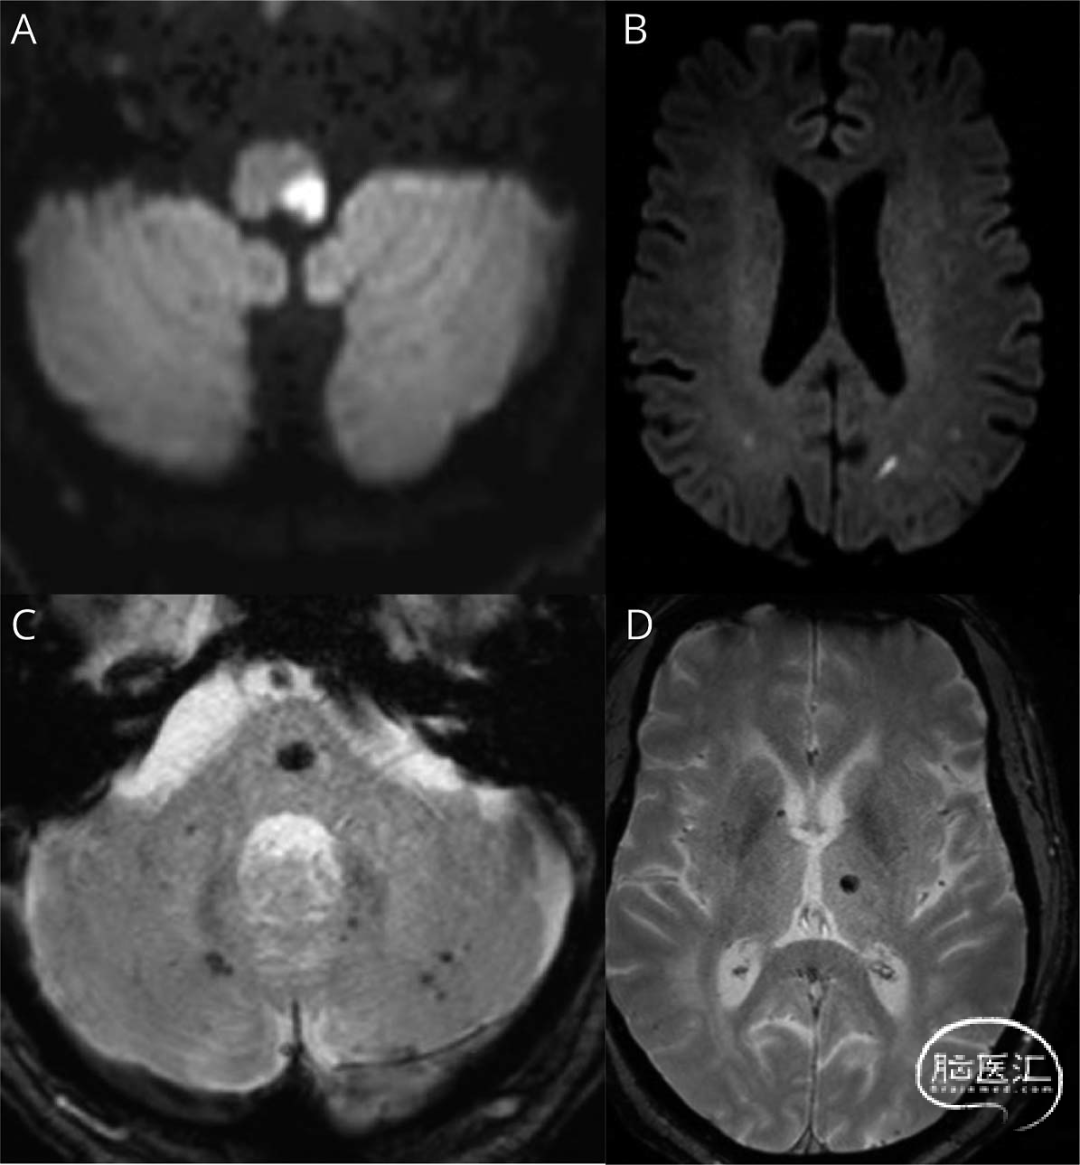

一名59岁男性,有未确诊的高血压史和6年前二尖瓣瓣环成形术史,醒后出现剧烈恶心、旋转性眩晕和头痛。入院时神经系统检查显示:凝视诱发左向共轭性眼震、左侧霍纳综合征、失声、右上肢温度觉缺失、左上肢小脑性共济失调,符合瓦伦贝格综合征表现。脑MRI证实左侧延髓超急性卒中(图1A)。鉴于弥散加权成像与液体衰减反转恢复序列存在不匹配表现,经与认证卒中神经专家讨论后,由神经科高级注册医师实施静脉溶栓治疗。患者随后被转入综合卒中中心接受标准化治疗。

24小时复查脑MRI确认左侧延髓梗死,并发现多区域超急性缺血灶(图1B),归因于为降低溶栓出血风险而初始进行的积极降压治疗。同时发现幕上及幕下多发急性微出血灶(图1C、D),考虑与溶栓治疗及初始高血压有关。经历需要长期ICU住院的复杂临床过程后,患者最终康复,仅遗留左侧面部及右上肢感觉减退,伴左上肢共济失调和步态不稳。

图1 脑磁共振成像(MRI)。急性期轴位弥散加权成像(DWI)(A)显示左侧延髓卒中。24小时后复查轴位MRI(含DWI序列)(B)显示新发大脑半球深部分水岭区病灶;小脑水平磁敏感加权成像(SWI)(C)与丘脑水平SWI(D)显示幕上及幕下多发急性微出血灶: